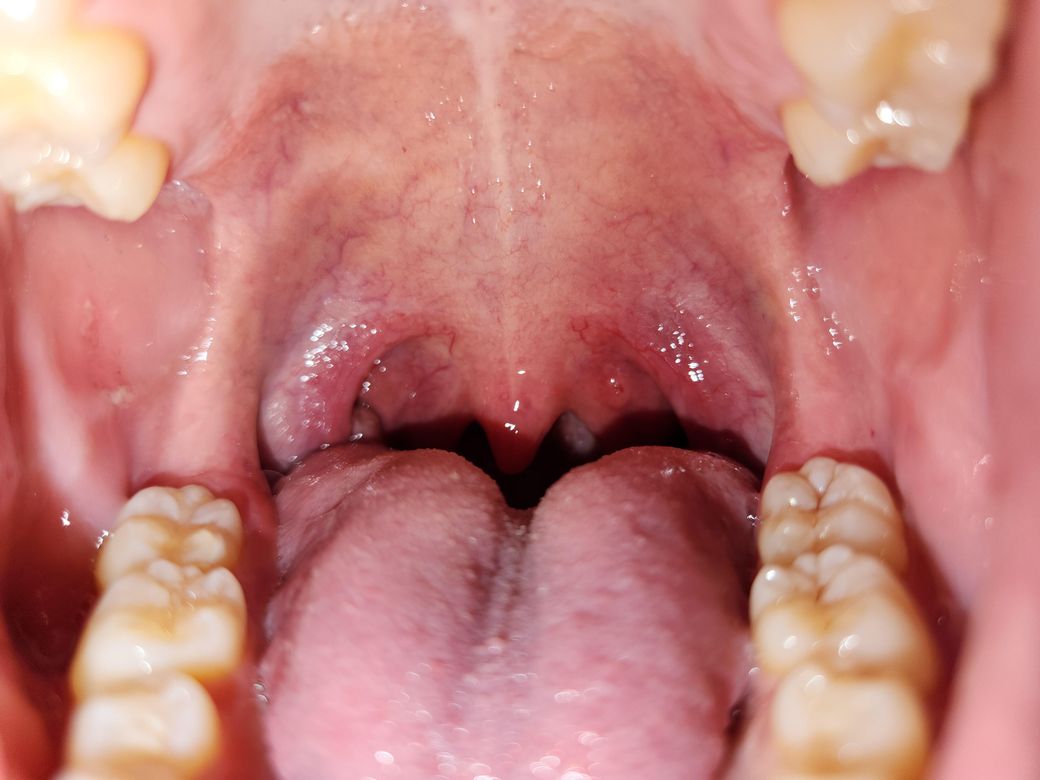

왼쪽 목구멍 윗쪽에 뭐가 났는데 이게 뭘까요...?

이따금씩 구내에 생기는 수포같은건줄 알고 손 씻고 터트리려고 했지만 터지진 않고 생각보다 단단한? 느낌이더라고요.

검색해보니 비인두암이라는 무서운 암일까 걱정이 많이 됩니다... 당연히 병원에 가고 싶지만 현재 미국 출장 중으로 4주 후 귀국 예정입니다 ㅜ

• 1번 째 사진

올려주신 사진으로 미루어 악성 병변보다는 양성 질환의 가능성이 더 생각되나 귀국 후 이비인후과 진료를 받기 바랍니다.

음주, 흡연, 카페인, 자극적 음식의 섭취와 과도한 목 사용을 피할 것을 권합니다.